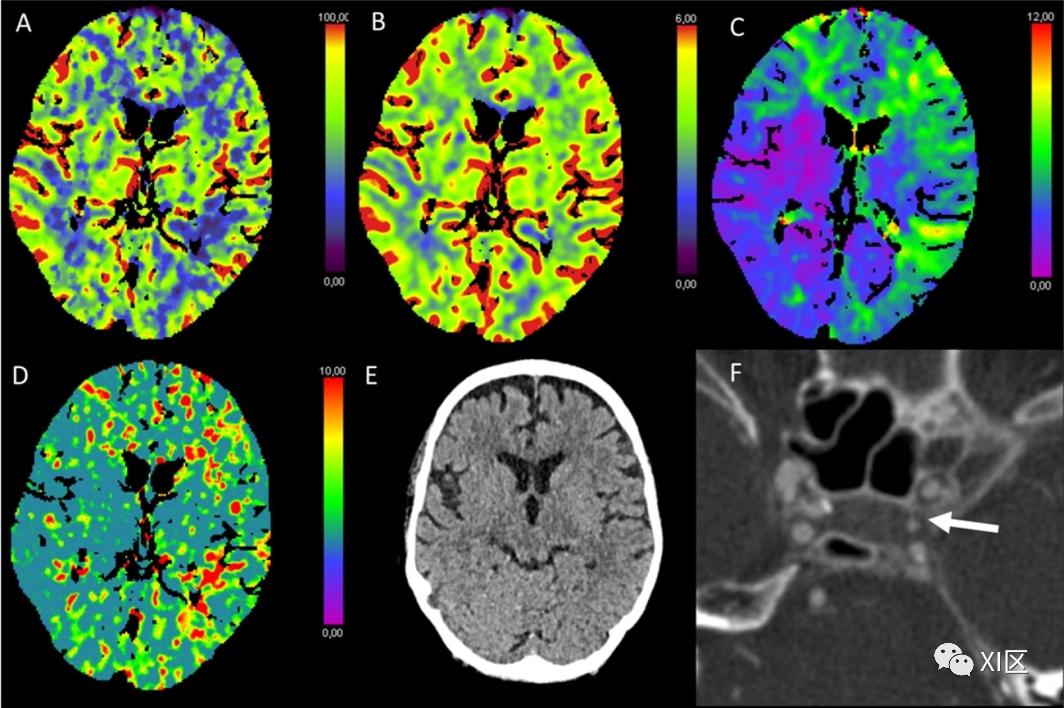

图1、图2、图3和图4给出了急性幕上卒中的例子。图5是一个恶性右侧MCA梗死的随访检查。

图2 脑部CTP生成的彩色编码图:(A)脑血流量(CBF)[mL/100 g/min],(B)脑血容量(CBV)[mL/100 g],(C)Tmax [s],以及(D)平均通过时间(MTT)[s]。(E)NECT和(F)动脉CT血管成像(CTA)。该患者在经导管主动脉瓣植入术(TAVI)后出现了左侧的暗区。在NECT图像上,只有大脑皮层有轻微的低密度改变,右枕部皮层有轻微的脑肿胀。CTP显示该区域的CBF和CBV降低,Tmax和MTT延长。CTA图像上没有发现明显的血管闭塞。